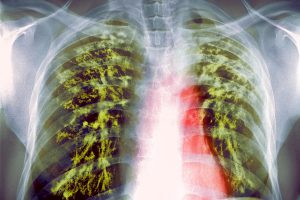

Где локализуется боль при туберкулезе

Туберкулез – заболевание, характеризующееся поражением легких. Болезненные ощущения при этом возникают в области грудной клетки. Зачастую они переносятся достаточно тяжело, особенно в период обострения патологии. Но не всегда могут означать туберкулез. При постановки диагноза врач обращает внимание и на сопутствующие проявления.

Боли при туберкулезе легких сопровождаются и другими симптомами. Пациенты часто жалуются на:

1. Кашель. Может иметь различную интенсивность, а вместе с мокротой при тяжелом поражении выделяется кровь.

2. Затрудненное дыхание.

3. Одышка, возникающая сначала при больших физических нагрузках, а затем даже при незначительных движениях.

Болезненные ощущения также возникают в области грудины и с течением времени усиливаются. Сильная боль ощущается во время кашля, после которого наблюдается затрудненность дыхания.

Характер болей

Боль при туберкулезе легких может носить различный характер. Чаще всего наблюдается колющая и острая. К возникновению неприятного симптома приводят дыхательные движения.

Но болевые ощущения всегда носят нарастающий характер, особенно на начальном этапе развития заболевания. При остром течении становятся постоянными и не проходят даже в состоянии покоя, становятся нестерпимыми.